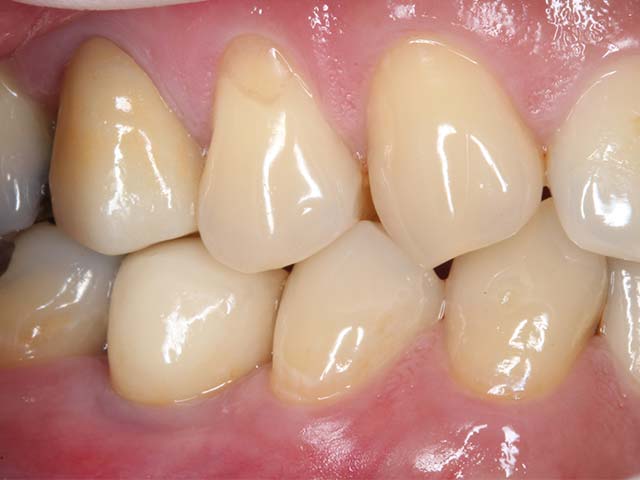

六年追蹤

美觀功能良好